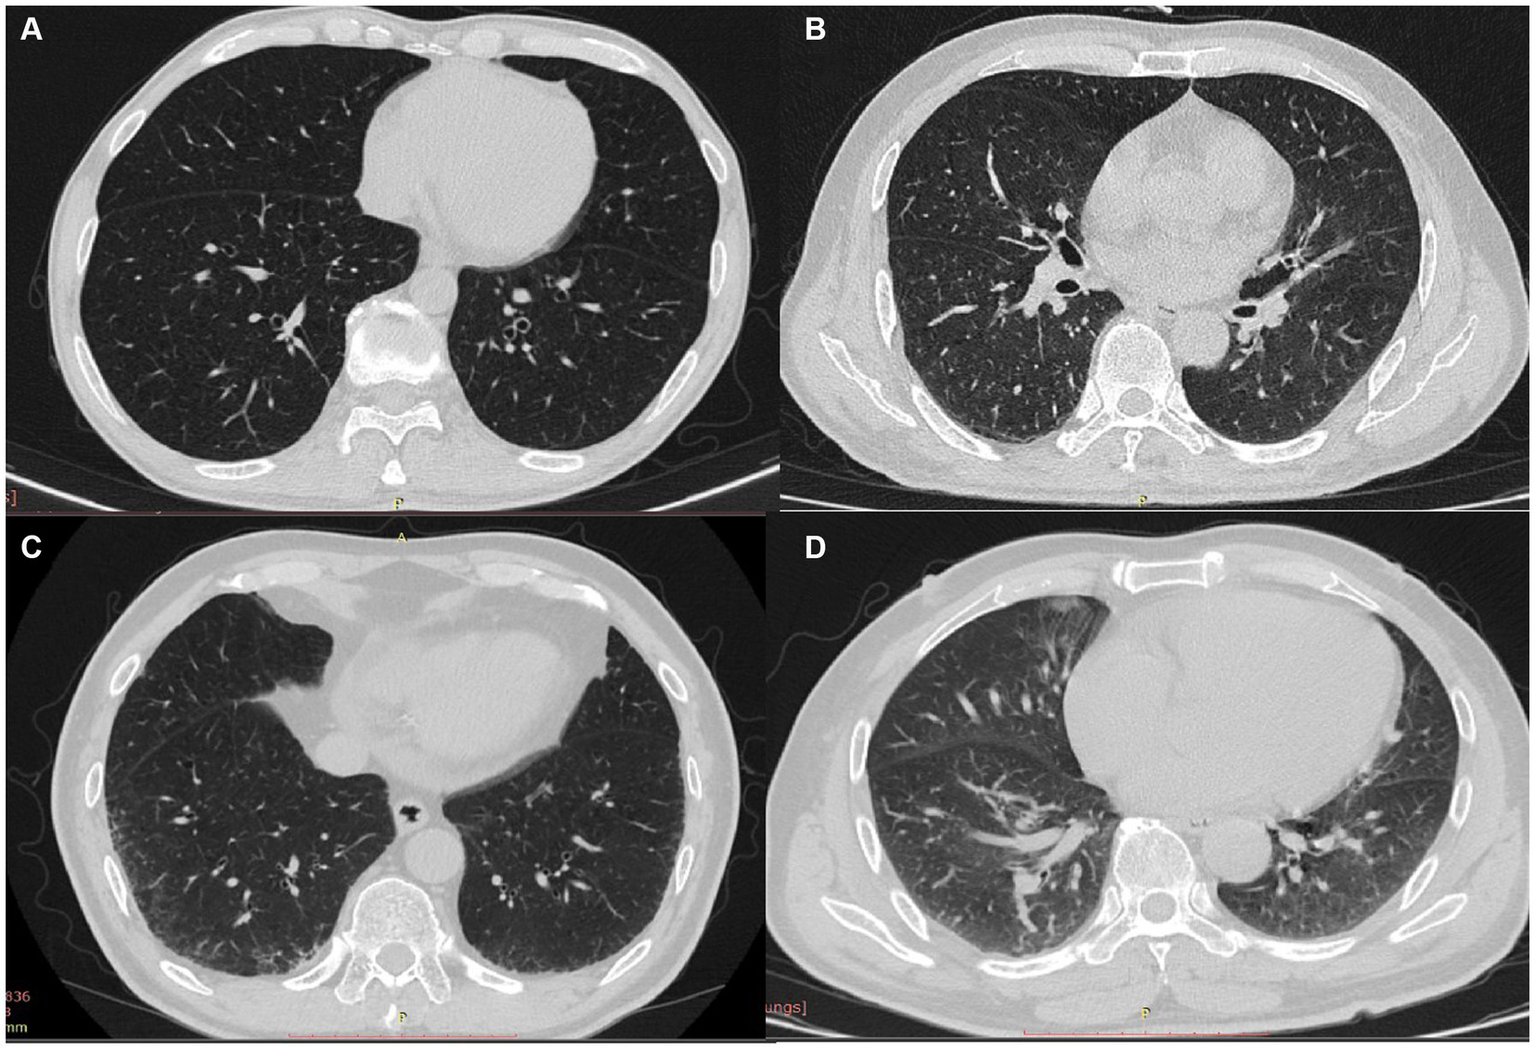

Representative imaging findings of COPD patients without ILA and with equivocal/definite ILA are shown in Figure 3. Table 2 presents radiologic findings of chest CT scans in patients with equivocal and definite ILA. The most common radiologic findings of equivocal and definite ILA patients were focal or unilateral reticulation (73.9%) and nondependent ground-glass opacity (59.5%), respectively. The ILA scores of definite ILA tended to be higher than the patients with equivocal ILA (1.22 ± 0.52 vs. 2.93 ± 1.72).

Figure 3

(A–D) CT findings of COPD patients without ILA and with equivocal/definite ILA; patients without ILA (A) and characteristic images of equivocal/definite ILA (B–D), including unilateral reticulation (B), bilateral reticular opacities (C) and nondependent group-glass opacity (D).